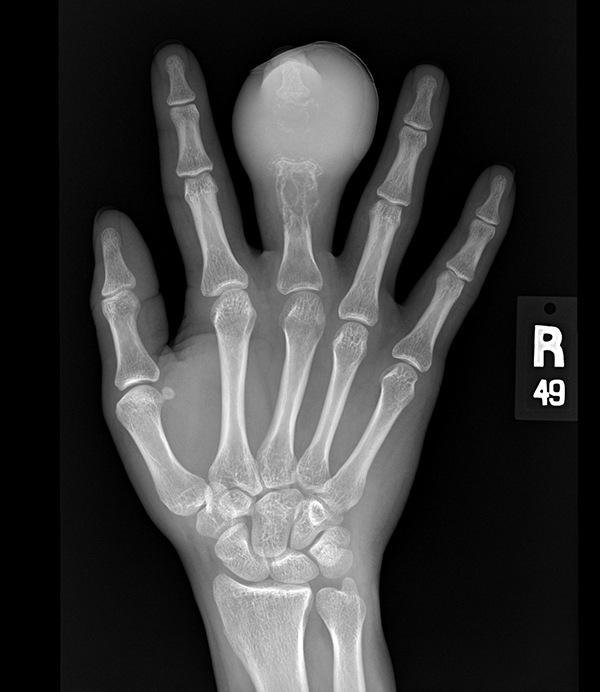

Первичный осмотр дополняется рентгенографическим исследованием кости, которое и показывает наличие опухоли (когда самой опухоли еще не видно, можно определить соседние участки кости, которые уже вовлечены в опухолевой процесс).

При костной саркоме рентген покажет нечеткие слои кортикальной пластинки костной массы, изменение мягких тканей. При этом очаги обызвествления и патологические хрящевые включения будут отсутствовать.

Базовым методом обнаружения саркомы Юинга является рентгенография: она дает возможность визуализировать опухоль, определить ее размеры и стадию развития. Особенности рентгенологической картины при исследовании костей, пораженных саркомой Юинга:

- комбинация остеосклеротического и деструктивного процессов костеобразования;

- расслоение, нечеткость контуров и разделение на волокна кортикального слоя;

- мелкие игольчатые и пластинчатые формирования в структуре надкостницы;

- изменение мягких тканей возле опухоли, которое зачастую превышает ее по размерам;

- отсутствие в мягкотканном компоненте хрящей, кальцинатов и элементов патологической костной ткани.